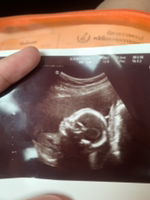

นี่เจอตอน 8week คะ อดทนรออีกนิดนะคะแม่ 🥰

6 w 2 d ค่ะ พร้อมหัวใจเต้น

เพิ่งไปซาวด์มาวันนี้เลยค่ะ 6 วีค ซาวด์ทางช่องคลอดค่ะ ถึงเห็นตัวและได้ยินเสียงหัวใจแล้ว ซาวด์ทางหน้าท้องไม่เห็นค่ะแม่ ยังไงแม่รออีกหน่อยนะคะ อย่าเพิ่งเครียดค่ะ

บ้านนี้8วิคค่ะ ทั้งหัวใจทั้งตัวน้องเลยคะ

8w3dจ้า เจอตัวน้องกับเสียงหัวใจ